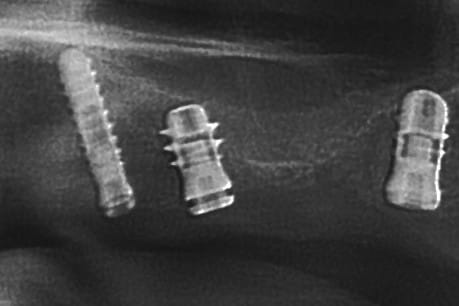

ce qui me frappe, tout de même, avec les quelques radios prises, c'est la cicatrisation osseuse au niveau de ceux en 15 et 25 (cf panos jour de la pose/3mois/4mois et les "zooms" pose/4mois)

Oups, le 2e implant en secteur 1 en partant du fond...

Celui qui est court, avec les spires distales dans le vide, enfin, il me semble...